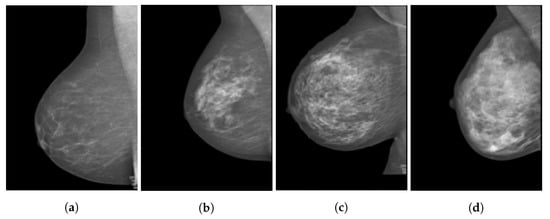

The heterogeneity of the tissue makes it difficult to generate standard numerical and physical models, especially since breast density varies from patient to patient. This density is not the numerical ratio of mass to volume, as used in Pennes’ BHE, but rather, a descriptive ratio of fibroglandular to adipose tissues. The more fibroglandular tissue is present, the denser the breast. This breast density can be classified into four categories defined by the American Cancer Society []. A comparison of such breast density can be observed in Figure 2, where the four images from (a) to (d) show magnetic resonance imaging (MRI) scans of breasts with increasing fibroglandular tissue composition.

Figure 2.

Sagittal cross-section of breast MRI scans showing the breast density variations: (a) almost entirely fat, (b) scattered fibroglandular tissue, (c) heterogeneous fibroglandular tissue, and (d) extreme fibroglandular tissue. Images from [].